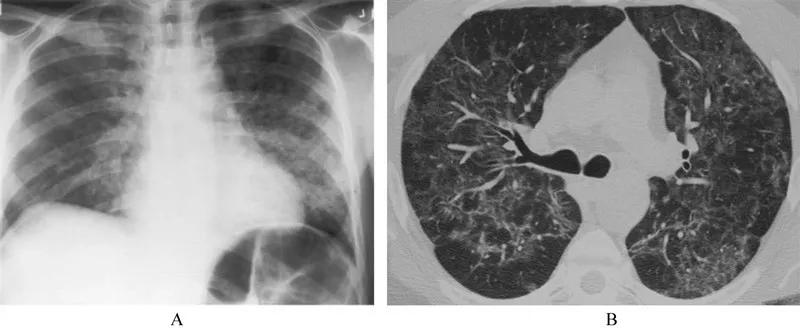

典型的X线胸片表现是自肺门向外放散的双侧弥散性浸润影(图1A),但是各种非典型性表现(各种密度的结节影,空洞)也有报道。一旦发生气胸,其治疗往往是困难的。在肺孢子菌肺炎的早期,X线胸片可以是正常的,但是在此期,肺部高分辨CT可能会表现毛玻璃影(图1)。

图1 肺部CT

A. 在HIV感染合并PcP的患者X线胸片表现为弥漫性浸润;B.在HIV合并PcP感染的患者肺部高分辨CT显示毛玻璃影